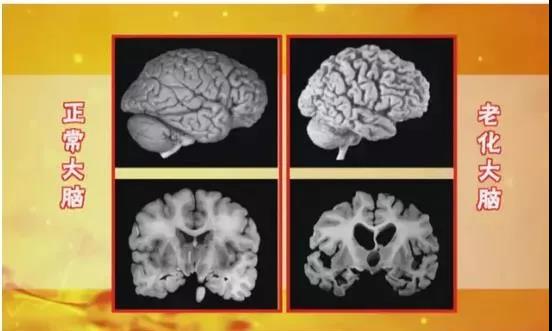

大脑在25岁左右,神经细胞逐渐减少,脑重量约1400g;脑重量在40岁后随年龄增长而减轻,60岁后变化比较明显,比我们年轻时减轻约6%-8%,表现为脑皮质变薄、脑回变窄,脑沟加宽、脑室体积扩大。